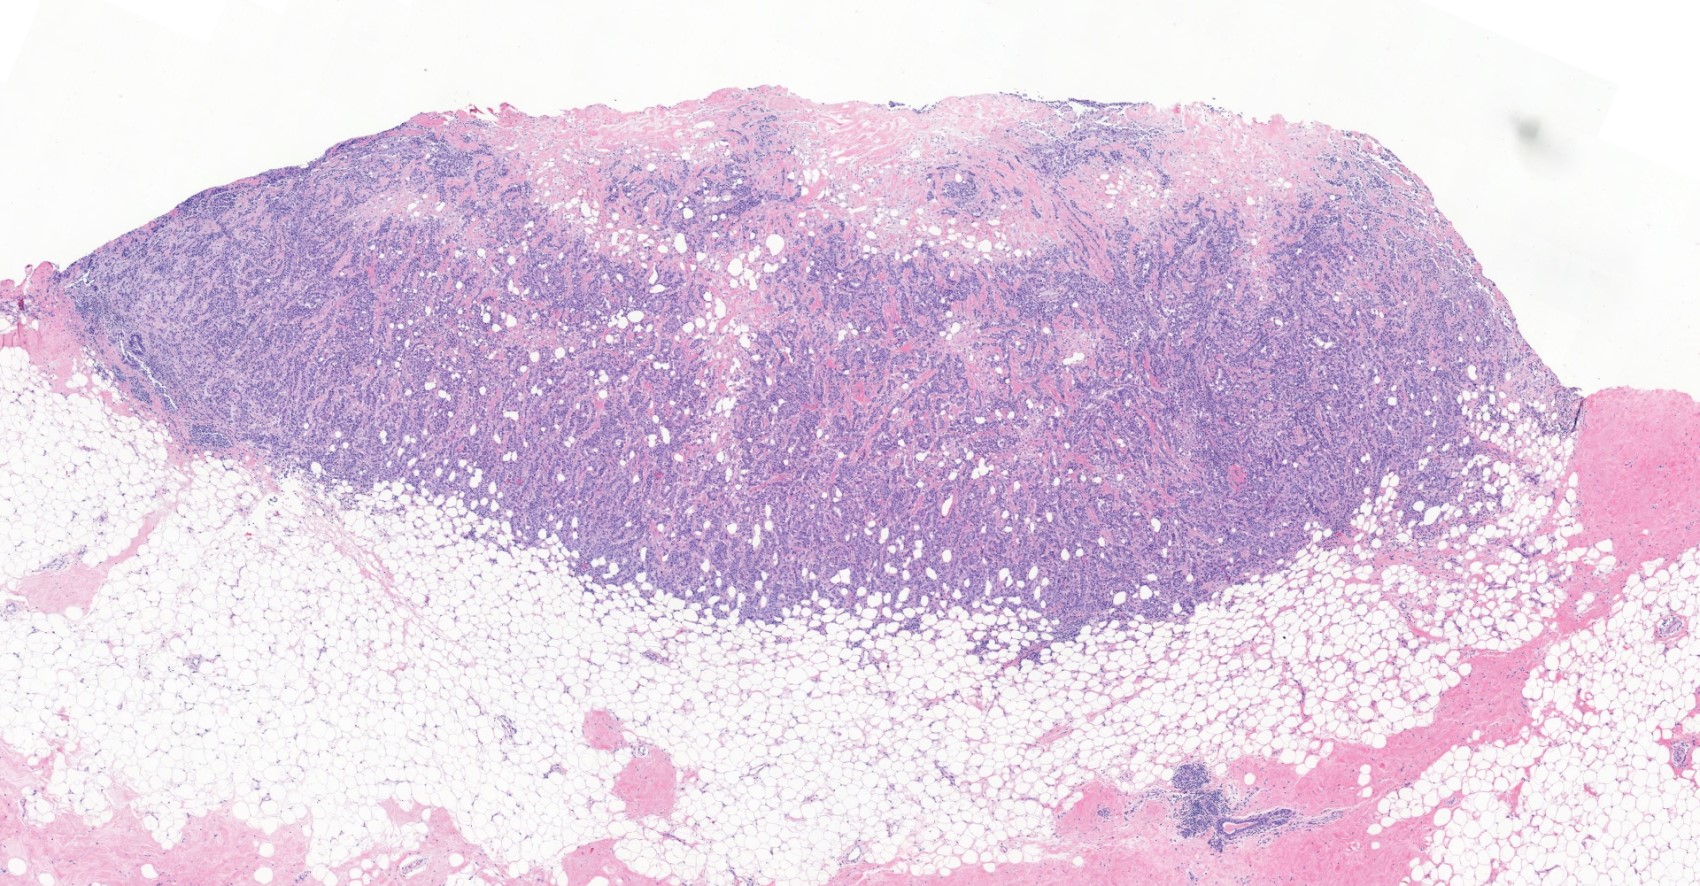

Microscopic (histologic) images

Contributed by Julie M. Jorns, M.D., Kristen E. Muller, D.O., Gary Tozbikian, M.D. and Emad Rakha, M.D.

- Histological features of IBC NST vary considerably from case to case and even within the same case

- Margins vary from highly infiltrative, permeating the surrounding tissue, to continuous pushing margins

- Large and solid nests or syncytial infiltrative growth pattern with little associated stroma and an expansive growth that compresses the surrounding stroma (e.g., most basal-like breast cancers)

- These tumors typically show high histological grade, a prominent tumor associated lymphocytic (TIL) infiltrate, a triple negative phenotype and often have basal-like molecular profiles